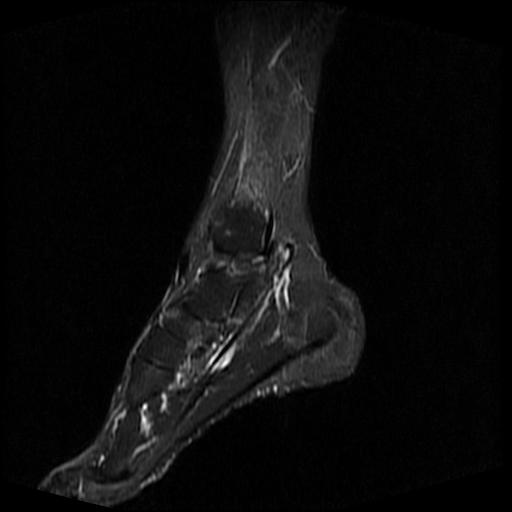

标题: MRI0968:女性,70岁,跟骨信号异常 [打印本页]

标题: MRI0968:女性,70岁,跟骨信号异常

女性,70岁,右侧跟骨疼痛2个月,负重时加剧,不负重时不疼。

跟骨cr片正常。

跟骨病灶呈片状,边界模糊,可否考虑隐匿性骨折呢?

跟骨长t1长t2信号异常,边缘模糊(肿瘤一般边界清楚,故肿瘤不考虑),压脂像呈高信号--骨髓水肿(炎症?)。